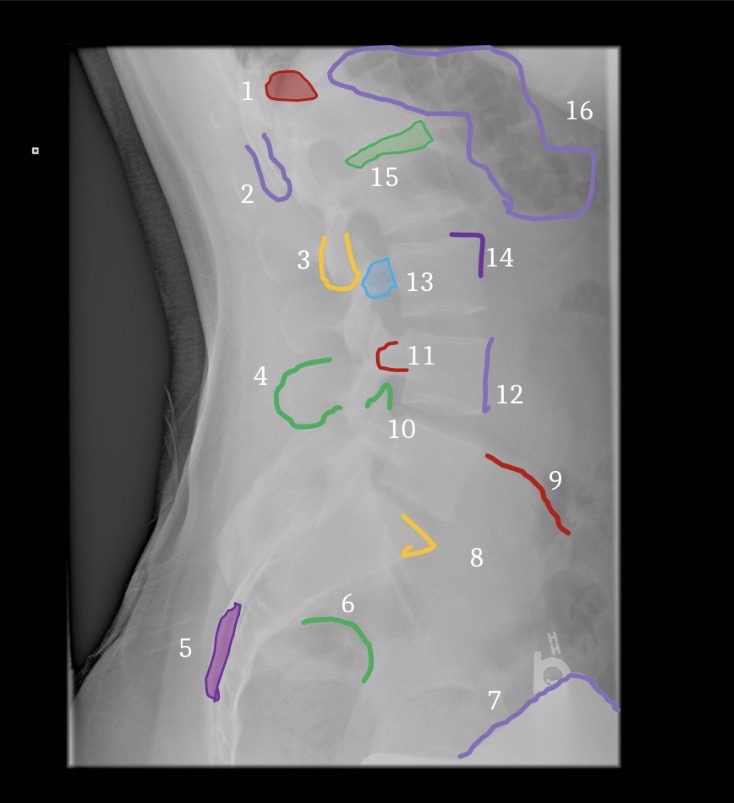

1

Inferior Margin of right 1th rib

2

Spinous process of T12

3

Left pedicle of L2

4

Left transverse process of L3

5

Right facet joint space L2-3

6

L4 spinous process

7

Inferior margin of right lamina L5

8

Right sacral ala

9

Superior margin right 1st anteror sacral foramen

10

Left margin of sacrum

11

Left iliac crest

12

Left posterior iliac spine

13

Superior margin left acetabulum

14

Gonadal shielding

15

Gas in colon

16

Inferior margin of liver